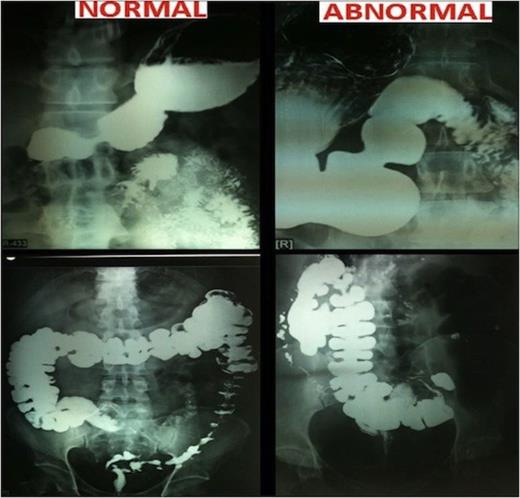

A 32 yr old morbidly obese female weighing 111 Kg and BMI of 41.41 was electively admitted to the hospital. She had tried a number of diet and exercise programmes but failed to sustain reduced weight loss. She was a known case of partial situs inversus as diagnosed earlier during her pregnancy few years ago. She underwent standard pre-operative workup including physician, psychological and anaesthetic assessment satisfying our selection criteria for surgery. This Grade 3 obese patient suffered from cough, dyspnoea and chest pain. She had no history of diabetes or Ischemic heart disease though blood pressure was 130/80 mmHg. Her general examination and preoperative investigations were within normal limits. Heart sounds were normal and on the left side in the chest. Abdominal girth was increased. Preoperative barium follow through under fluoroscopic control showed situs inversus with malrotation of gut. Stomach was on the right side, normal in shape, increased size, normal mucosal pattern, no ulcer. Duodenal C Loop was opposite. Small bowel on right side and normal, no narrowing. Ileocecal junction, caecum and appendix was in left iliac fossa. Descending and sigmoid colon located on the right side close to ascending colon. CT scan of chest/abdomen and pelvis showed enlarged mediastinal lymph nodes and situs inversus. Patient was admitted one day prior to surgery and LSG was performed in January 2011. Following general anaesthesia, patient was placed in reverse Trendelenberg position. Primary operating surgeon stood on the left side of the patient as contrast to usual right side. Trocar positions were also mirror imaged. Operative feel was uncomfortable; as in a right handed person writing by a left hand. Entire upper quadrant was occupied by the liver. Enlarged spleen was in the right side. Orogastric tube negotiation was difficult because of the position of the stomach. Primary surgeon had to come to right side to reach to the right crus. Most of the time single hand technique had to be used instead of both hands. Surgical time was 90 minutes.